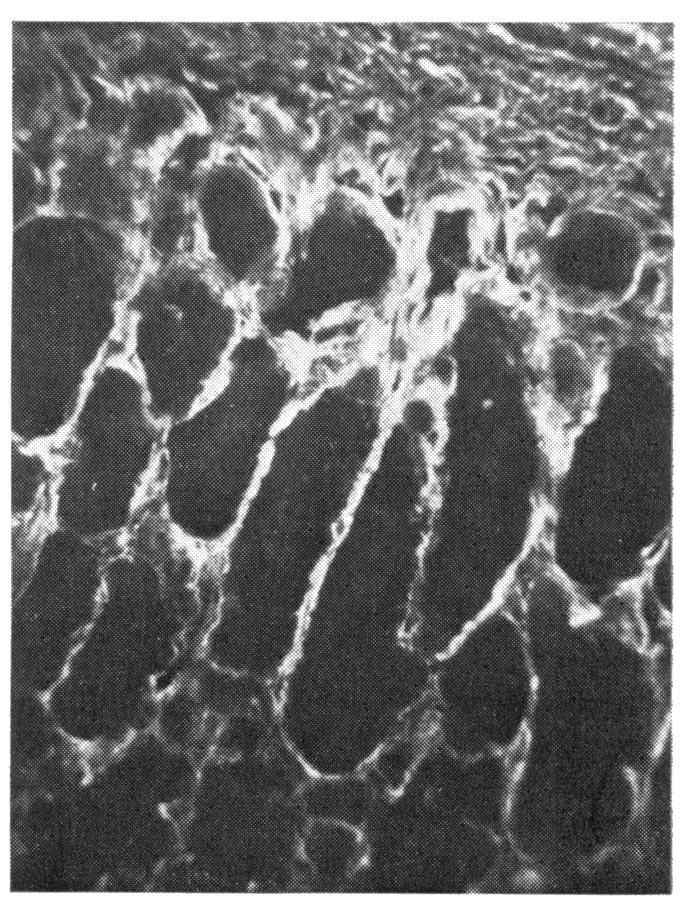

Reticulum fibres in relation to retinal vessels.

Argyrophilic perivascular and intervascular fibres in the mammalian retina are shown by specific antireticulin immunofluorescence to consist of reticulin. The possible significance of these findings is briefly discussed.